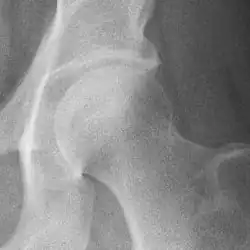

Hip joint with no signs of osteoarthritis.

The most commonly used radiographic classification system for osteoarthritis of the hip joint is the Kellgren–Lawrence system (or KL system).[6] It uses plain radiographs.

Osteoarthritis of the hip joint may also be graded by Tönnis classification. There is no consensus whether it is more or less reliable than the Kellgren-Lawrence system.[8]

Severe (Tönnis grade 3) osteoarthritis of the hip.

Tönnis classification[9]

Grade Description

0No osteoarthritis signs

1Mild:

• increased osteosclerosis

• minor joint space narrowing (normal joint space is at least 2 mm at the superior acetabulum)[7]

• no or minor loss of head sphericity

2Moderate:

• small bone cyst

• moderate joint space narrowing

• moderate loss of head sphericity

3Severe:

• large bone cysts

• severe joint space narrowing, or joint space obliteration

• severe deformity of the head